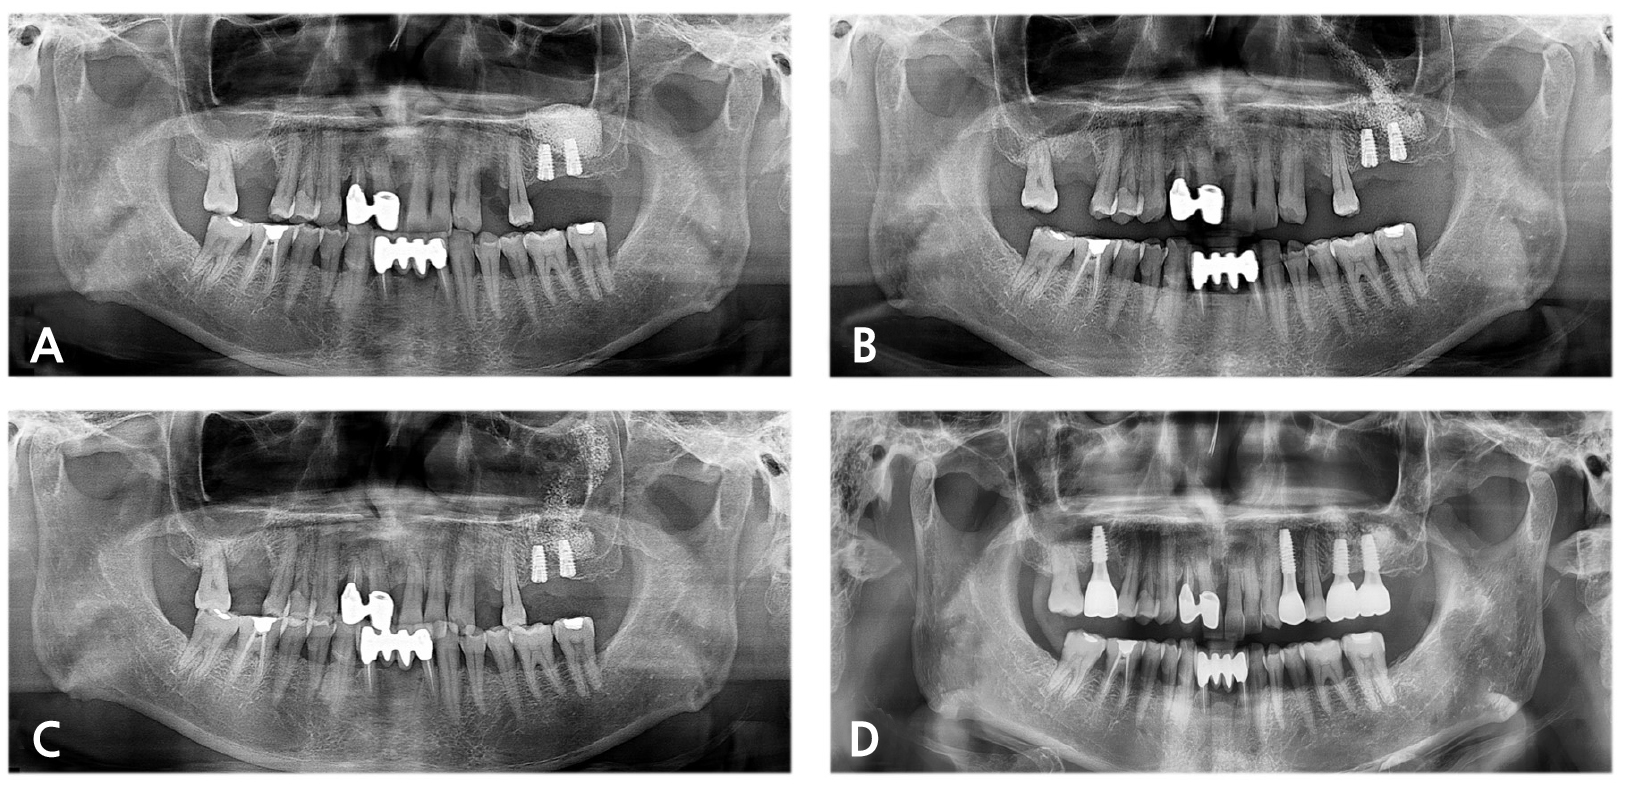

A 61-year-old male (patient 4) visited the Department of Oral and Maxillofacial Surgery for dental implant placement on the left posterior maxilla. SALW with bone substitute and placement of dental implants were simultaneously performed. Immediate postoperative radiographic examination revealed the intact status of the mucosal lining and bone augmentation of the left maxillary sinus (Fig. 4A). Ten days after the procedure, however, the patient complained about purulent nasal discharge, foul odor and headache on the ipsilateral side. After taking PAN showing the migration of bone graft material, lavage and removal of bone graft material from the sinus cavity were performed (Fig. 4B). Subsequent PAN showed scattered bone graft material in the sinus cavity, and further lavage was performed (Fig. 4C). During the follow-up period from the lavage procedure on the sinus cavity, symptoms of acute maxillary sinusitis subsided. At four months after implant placement and SALW, favorable osseointegration was confirmed, and the definitive prosthesis demonstrated favorable clinical and radiological findings at 18 months after delivery (Fig. 4D).

Fig. 4.

(A) Immediately postoperative PAN of patient 4 revealed no remarkable findings on the left maxillary sinus. Ten days after SALW, (B) PAN showed migration of graft material and opacification in the left maxillary sinus. During the lavage of the maxillary sinus, (C) PAN still showed disseminated graft material within the maxillary sinus, (D) Eighteen months after the definitive prosthesis delivery, no remarkable pathologic condition was identified.